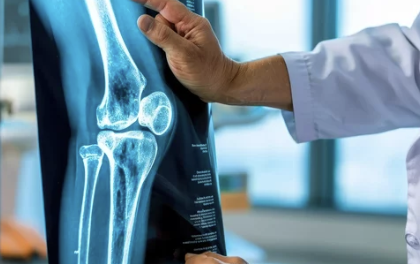

3. 무릎 관절삼출 진단 방법

✅ 병원에서 진행하는 주요 진단 검사

검사 방법 설명

| X-ray 검사 | 무릎 관절의 골절, 뼈의 이상 여부 확인 |

- 무릎 관절염과 연골 손상 여부를 구별하기 위해 MRI 검사가 효과적입니다.